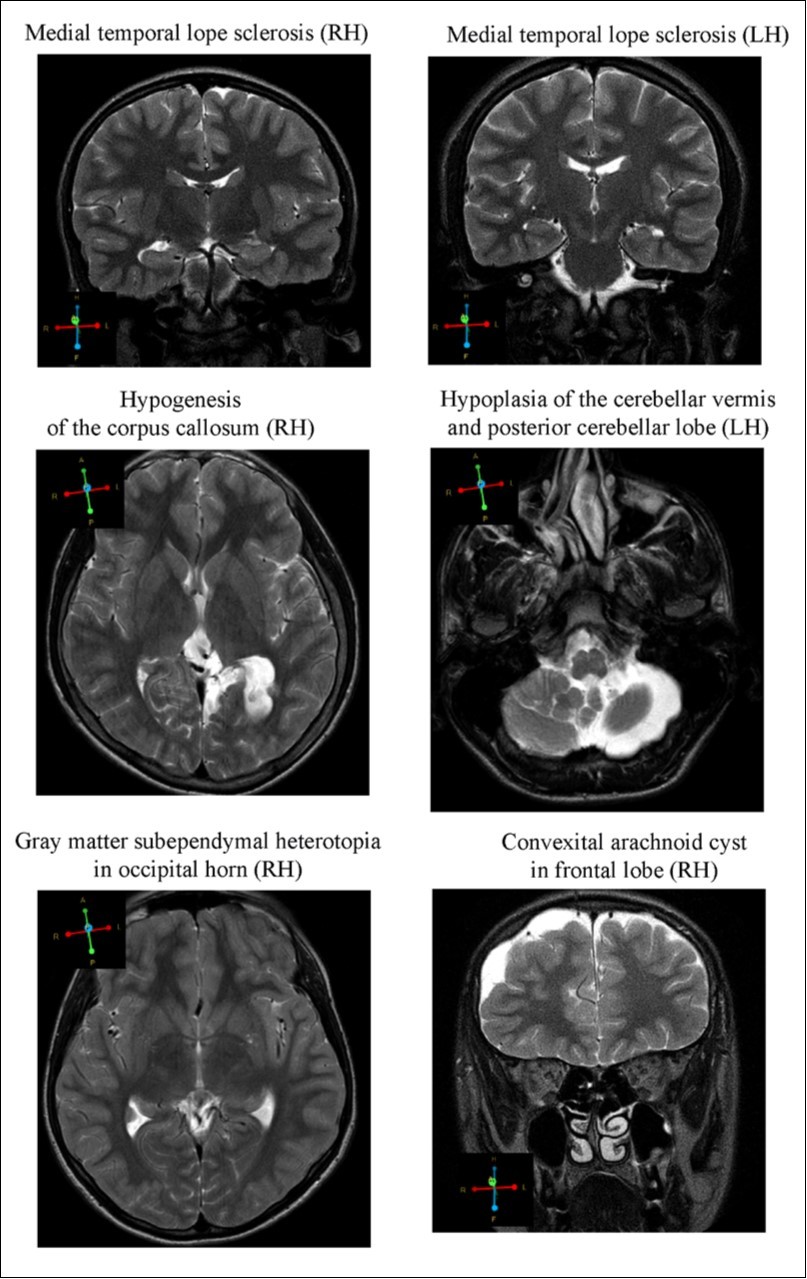

MRI

MR images revealed alterations in brain tissue only in boys with CD (n = 10), however there was no statistical significance between brain malformation and CD. Cerebral dysgenesis was the most prevalent brain abnormality. CD subjects displayed (Figure 2); 1. Medial temporal lobe sclerosis (hypotrophy of either right or left hippocampus) (n = 2); 2. Hypogenesis of the corpus callosum i.e. the band of white matter connecting the two hemispheres of the brain, failed to develop normally and was thinner than in healthy subjects (n = 1); 3. Gray matter heterotrophy, a type of cortical dysplasia, which results in the mislocation of neurons during neuronal migration (n = 2); 4. Arnold-Chiari malformation type II, characterized by a downward displacement of the cerebellar tonsils (hypoplastic cerebellum) through the foramen magnum (n = 1); 5.Arachnoid cysts in the temporal lobe and frontal convex (n = 2). All but two of the subjects described above had mothers with a history of stress and/or various complications during pregnancy and/or labor. Moreover, subjects with the described brain malformations showed signs of epilepsy and/or ADHD they have been excluded – in CD people. Only one subject, having corpus callosum hypogenesis and gray matter heterotrophy in the parietal lobe, showed mild neurological symptoms, having conduct disorder with intellectual disability

Figure 2.Representative images of the brain abnormalities observed in some children with the tendency of antisocial behavior (AST) by Magnetic Resonance Imaging (MRI). Coronal sections (4 mm thick) were acquired by T2 turpbo spin echo (TSE) multi vane (MV) sequence; Axial sections (6mm thick) - T2 TSE.